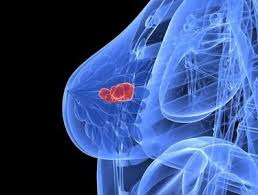

ब्रेस्ट कैंसर.

अच्छी लगती है अंग्रेजी, कभी कभी

दे देती है भावों को भाषा का आवरण

भदेस क्या! शुद्ध सुसंस्कृत भाषा में भी,

नहीं उचार या बोल पाते.

स्तन – स्तन का कैंसर

जितने फर्राटे से हम बोलने लगे हैं –

ब्रेस्ट – ब्रेस्ट कैंसर!

नहीं आती है शर्म या होती है कोई झिझक

बॉस से लेकर बाउजी तक

डॉक्टर से लेकर डियर वन्स तक को बताने में

ब्रेस्ट कैंसर, यूट्रेस कैंसर.

यह भाषा का सरलीकरण है

या भाव का भावहीनता तक का विस्तार

या बोल बोल कर, बार बार

भ्रम – पाने का डर से निजात

ब्रेस्ट कैंसर, ब्रेस्ट कैंसर, ब्रेस्ट

ब्रेस्ट, ब्रेस्ट, ब्रेस्ट कैंसर!

पॉप कॉर्न सा ब्रेस्ट!

पॉप कॉर्न सा उछलता

बिखरता ब्रेस्ट कैंसर।

यहां-वहां, इधर-उधर

जब-तब, निरंतर।

आने पर ब्रेस्ट कैंसर की सवारी

खोजते हैं आने की वजह?

लाइफ स्टाइल?

स्ट्रेस?

लेट मैरिज?

लेट संतान?

एक या दो ही बच्चे?

नहीं कराया स्तन-पान?

डॉक्टर और विशेषज्ञ हैं हैरान

नहीं पता कारण

नहीं निष्कर्ष इतना आसान

हर मरीज के अपने लक्षण

अपने-अपने कारण।